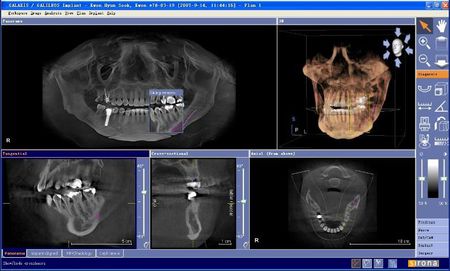

4)CT

電子計(jì)算機(jī)X線體層攝影,簡(jiǎn)稱CT。CT檢查的優(yōu)點(diǎn)是能避免影像重疊,使圖像非常清晰,具有很高的密度分辨力。對(duì)頜骨,牙齒進(jìn)行計(jì)算機(jī)斷層掃描,重建三維圖像,可多角度再現(xiàn)頜骨,牙齒內(nèi)部結(jié)構(gòu),各個(gè)組織間的關(guān)系。特別是對(duì)頜面部腫瘤的位置,范圍能提供較準(zhǔn)確的信息。